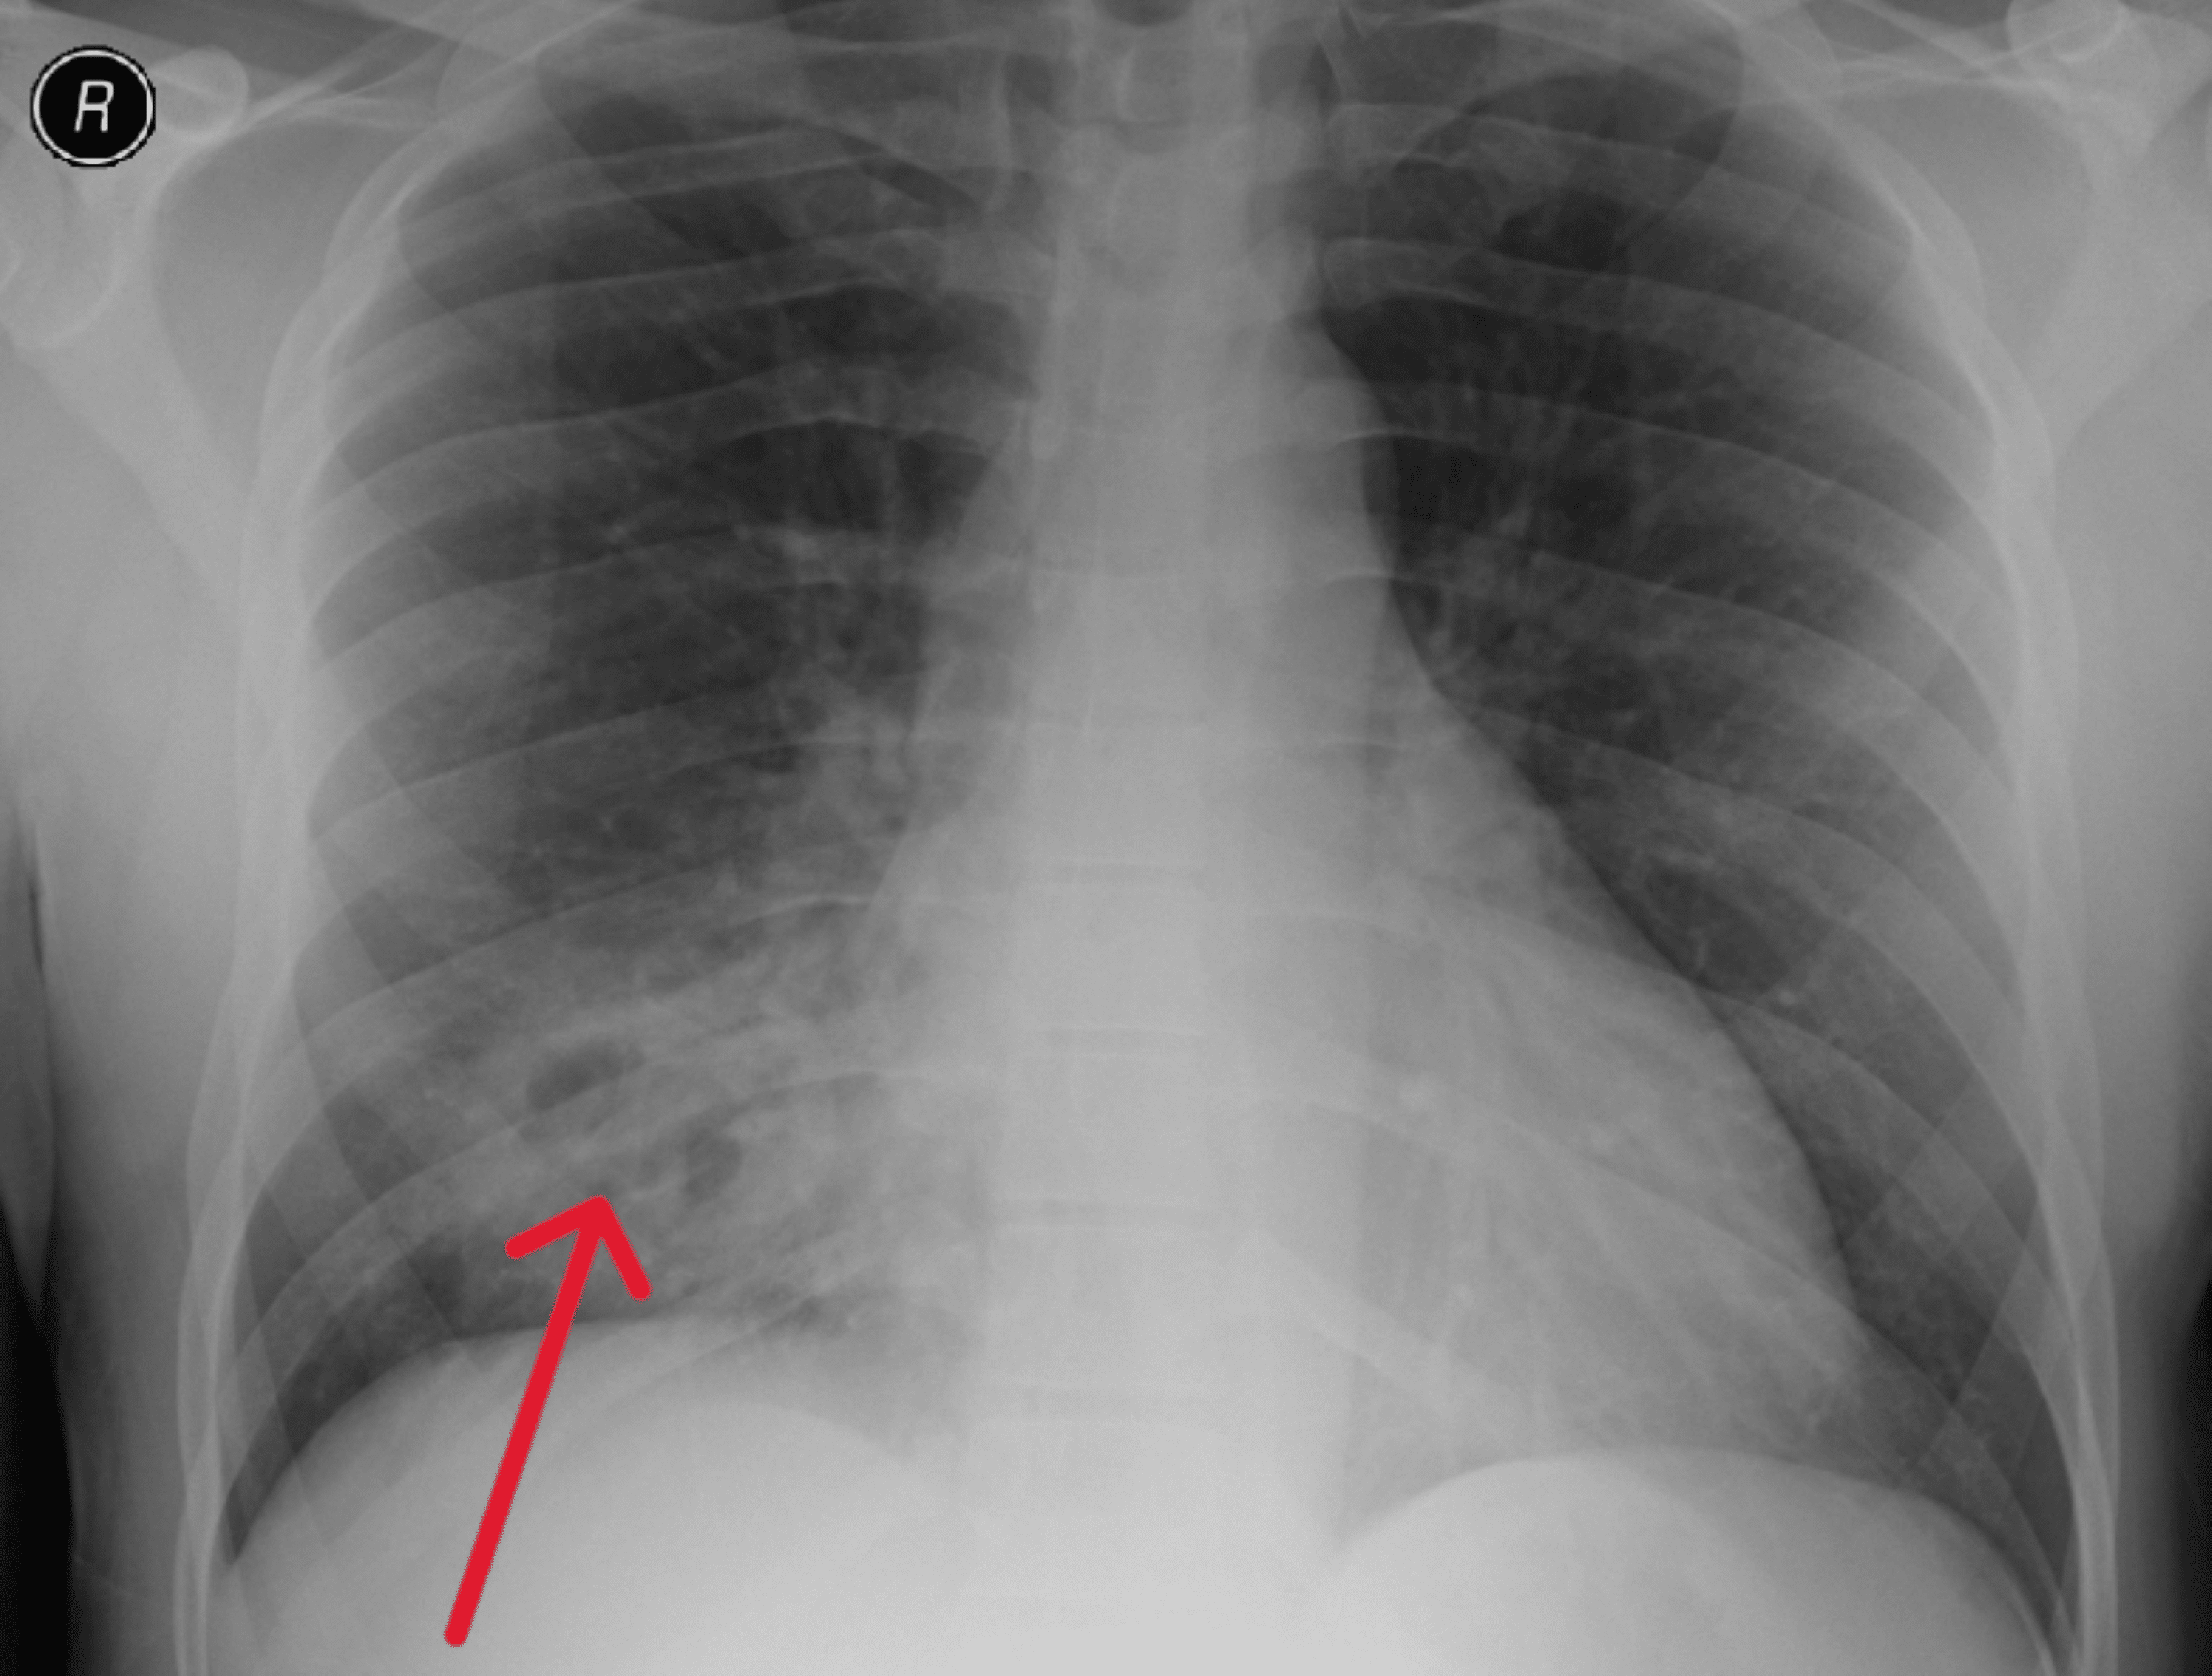

Necrotizing Pneumonia Radiology Differential Diagnosis Of Necrotizing Pneumonia While the term has been used synonymously with cavitating. Laboratory studies may also be helpful in diagnosing necrotizing pneumonia. It should be suspected in pneumonia. When compared to pneumonias without a necrotizing component, patients with necrotizing pneumonia. Necrotizing pneumonia represents a rare but serious complication of pneumonia in children. Necrotizing pneumonia refers to pneumonia characterized by the development of necrosis. Differential Diagnosis Of Necrotizing Pneumonia.

Necrotizing Pneumonia Radiology Differential Diagnosis Of Necrotizing Pneumonia The pattern of clinical decline may help differentiate patients with necrotizing. Necrotizing pneumonia represents a rare but serious complication of pneumonia in children. Cap is a common working diagnosis and is frequently on the differential diagnosis of patients presenting with a pulmonary infiltrate. While the term has been used synonymously with cavitating. It should be suspected in pneumonia. Necrotizing pneumonia. Differential Diagnosis Of Necrotizing Pneumonia.

necrotizing pneumonia Differential Diagnosis Of Necrotizing Pneumonia The pattern of clinical decline may help differentiate patients with necrotizing. Although reported in the literature, the streptococcus anginosus group (sag) is not often considered in the differential diagnosis of. Necrotizing pneumonia represents a rare but serious complication of pneumonia in children. Necrotizing pneumonia refers to pneumonia characterized by the development of necrosis within infected lung tissue. It should be. Differential Diagnosis Of Necrotizing Pneumonia.